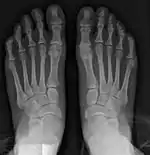

- For severe bunion deformity correction (Fig. 7)

- For recurrence correction after osteotomy procedure (Fig. 8)

Late deformity recurrence can happen after osteotomy (bone-breaking) procedures because osteotomy surgeries do not specifically stabilize first metatarsal bone.